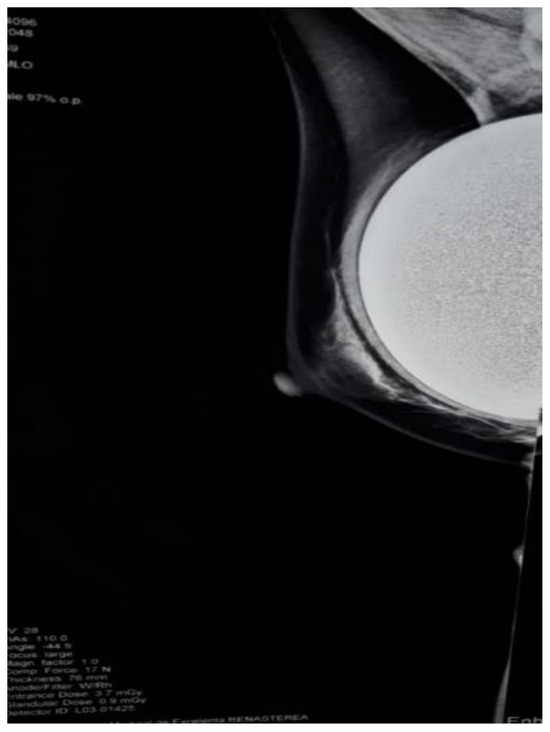

Physical examination revealed an approximately 3 cm solid tumor, mobile, located in the left axilla and another similar mass with a 1 cm diameter located in the superolateral quadrant of the left breast. The mass from the axilla was painful on palpation and the patient also complained of a slight pain that irradiated to the external chest wall. Blood tests revealed that the tumor markers CA- 125, CA15-3, CA19-9, and CEA were within normal limits. A mammography was performed and described the regular contour of the implant in the left breast with no other changes of the breast parenchyma (Figure 1).

Figure 1.

Mammography showing the regular contour of the left breast implant and no radiodense mass in the left axilla.